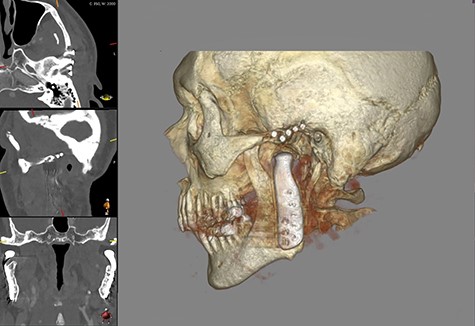

This report is about a 63-year-old patient suffering of bilateral deforming TMJ arthrosis (Wilkes-V) from a bilateral condylar fracture. In 2019 he presented himself to the Department of Oral and Maxillofacial Surgery, showing painful palpation above both TMJs and a severely decreased mouth opening (maximum interincisal distance of 1.5 cm). A computed tomography (CT) scan then revealed pathognomonic changes with flattening of the condyle and articular eminentia as well as partial ankylosis of the right TMJ (Fig. 1). Based on these findings, we decided for a bilateral TMJ-TJR. At this point, the patient only wanted one side replaced for the time being. After impressions were taken, plaster models were 3D-surface scanned and in combination with the CT dataset further processed by Zimmer-BiometTM (Warsaw, USA) for patient-specific TJR (PSI-TJR) fabrication. Another 3 months later, the TMJ-TJR of the right side could be carried out (Fig. 2). Postoperatively the patient received antibiotics for overall 7 days. Satisfied with the result, the patient requested reconstruction of the left TMJ 6 months later. With an improved mouth opening (2.8 cm), impressions were taken using an intraoral scanner. After PSI fabrication, the operation was carried out 9 months after (Fig. 3). Six weeks following surgery, the patient presented with a painful preauricular swelling on the left side, which was diagnosed as aseptic inflammation in the absence of erythema and pathologic joint puncture. Showing a periarticular edema, a broken screw and radial osteolysis around the drilling channels, a subsequent CT scan indicated the loosening of the ultra-high-molecular-weight-polyethylene (UHMWPE) fossa component (Fig. 4). In view of the long production time of new custom-made components and the damaged implant site, we decided to explant the fossa and to temporarily replace it with a non-fixed patient-specific spacer made of COPAL®-bone-cement (Fig. 5) (gentamicin and clindamycin additive) (Haereus; Hanau, Germany). The workflow included the surface scan of the original fossa-drilling template, the computer-aided design of a two-part press mould and the intraoperative fossa fabrication from COPAL®-bone-cement. With the use of a rubber elastic intermaxillary fixation, the vertical mandibular relation could be secured, painful movements and muscle shortening avoided and the risk of perioperative infection could be sufficiently minimized (Fig. 6). After 3 months without complications, the patient-specific COPAL® component could be removed and the new patient-specific UHMWPE fossa inserted within sufficiently regenerated bone (Fig. 7).

Shows postoperative CBCT after left TMJ replacement, 9 months after the right side.